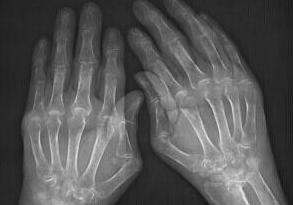

来院后,我院类风湿医生杜爱华主任立即为高女士安排检查。检查后发现高女士双手的近端还有指间及关节处会有关节肿胀的现象,并且双腕肿胀现象比较严重,下蹲困难,活动受限;最后确诊为类风湿性关节炎。

(图:体查、X线片检查都显示高女士类风湿病情严重)